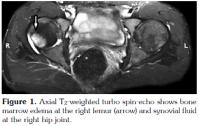

The typical MRI findings of AS are enthesisitis and ankylosis. However, at the very early stage of the disease, synovitis and and subcortical bone marrow edema are important diagnostic features. A number of studies have shown that subchondral bone marrow edema developes as a result of inflammation in various sites such as the sacroiliac joints, femoral heads, and the shoulders.[14-16] The sign of early involvement in AS is subcortical edema. Subcortical edema may be seen at the femoral head, symphisis pubis, and other sites of enthesis (Figure 1, 2). Histological studies have shown that the bone marrow edema in AS is in correlation with osteitis.[17] The femoral head bone marrow edema in AS differs from the diffuse form seen in septic arthritis, and it is more focal, frequently encountered in tendinous and ligamentous insertion sites. A similar pattern was present in the cases of our study (Figure 3). In one study, it was reported that 23% of cases with juvenile AS demonstrated subcortical edema at the symphisis pubis.[17] In our study, no bone marrow edema was encountered at the sites of the symphisis pubis of the patients. This fact may be due to the limited number of the patients enlisted in our study, and also to the difference in the patient age groups between our study and the study mentioned above.